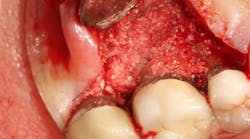

In other words, even experienced clinicians who access a root surface with flap surgery are sometimes limited in the amount of detoxification that can occur due to the depth of the defect and conventional instrumentation. (11) Further limitations with mechanical access to defects can come in the form of furcations with multirooted teeth. The diameter of the entrance to root furcation is usually smaller than the average tip of a curette, which can make access difficult (figures 1 and 1a). Molars with bone loss that includes furcations are often downgraded in prognosis due to this access difficulty. (12)

Figure 1: Molar with periodontal abscess due to furcation involvement